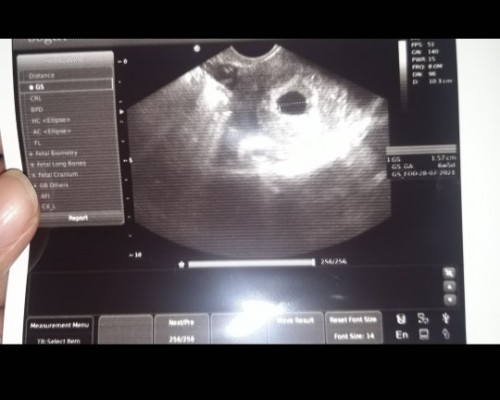

Saya sangat bersyukur pada Tuhan karena bisa merasakan suka duka kehidupan khususnya tentang kehamilan ini. Sebenarnya ini bukan kehamilan saya yang pertama karena pada Desember 2020 saya ditindak dokter untuk kuretase karena mengalami 'Blighted Ovum'. Saat itu saya sempat sedih, kecewa, dan marah karena beberapa hal; salah satunya penanganan medis yang agak lambat sedangkan saya sudah merasa kesakitan. Saya menginap di RS semalam dan keesokan harinya saya ditindak, syukurlah hari itu juga saya diperbolehkan pulang. Bersyukur juga suami mau mendukung saya saat itu untuk segera pulih. Dua minggu kemudian kami ke dokter, kami disarankan untuk menunggu 1 siklus haid untuk promil lagi, maka kami taati :) Saya hanya merasakan haid sekali, kemudian bulan berikutnya tidak. Awalnya saya kuatir, tapi saya memutuskan untuk test. Syukurlah saya positif hamil :) Kami memutuskan untuk menunda USG di awal kehamilan, tapi kami hanya memeriksanya ke bidan. Setelah berjalan beberapa minggu, mendengar detak janin saja membuat kami terharu betapa baiknya Tuhan karena ditempat mungil dan tersembunyi ini Tuhan ciptakan manusia dengan begitu ajaibnya.. USG pertama kalinya adalah saat usia kehamilan 20 minggu, karena saat itu kami mau bepergian ke luar kota (sebelum PPKM) dan perlu surat dokter. Saat melihat monitor USG, kami sangat terharu, karena bisa melihat tulangnya sudah terbentuk, detak janin normal bahkan jenis kelaminnya sudah bisa diketahui. Sekarang usia kehamilan saya memasuki 28 minggu, gerakannya makin terasa dan bayang-bayang persalinan semakin tergambarkan dalam pikiran. Saya sangat menikmati proses selama kehamilan ini (kenaikan berat badan, kurang nafsu makan sampai naiknya nafsu makan, pelupa, mood yang berubah-ubah, sembelit, lambat saat berjalan, susah tidur, dsb) karena kejadian sebelumnya yang Tuhan ijinkan untuk saya alami. Ternyata itulah yang membuat saya sangat mensyukuri proses ini. Menurut saya anak itu anugerah, titipan Tuhan. Ketika kita sudah dipercayakan-Nya, Tuhan juga yang akan memperlengkapi dan memampukan kita jadi orangtua yang terbaik bagi anak kita. Semoga cerita saya ini bisa membantu dan menginspirasi bahwa tidak ada yang mustahil dan tetap percaya waktu Tuhanlah yang terbaik bukan waktu kita. Berharap kita semua dalam keadaan sehat dan selalu sukacita :) Terimakasih. Foto 1: USG sebelum dinyatakan Blighted Ovum Foto 2: Hasil USG (25 minggu) #CeritaKehamilanTAP